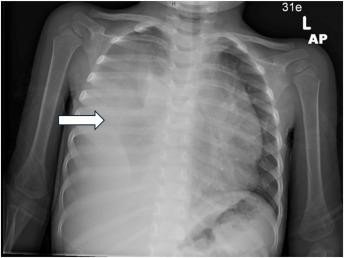

Figure: Thymic Hyperplasia